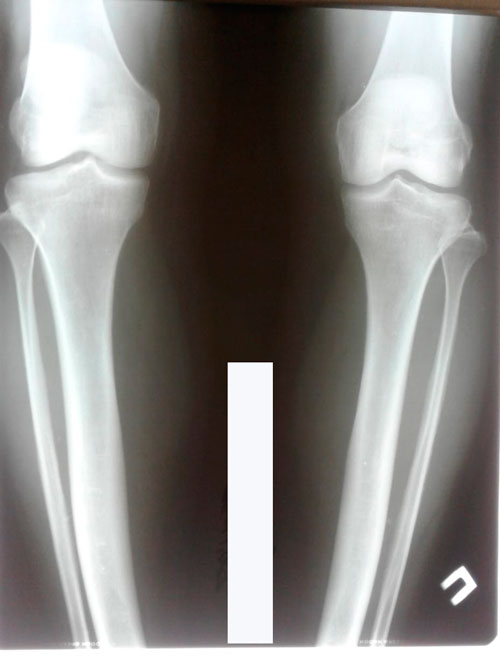

Исходник - 46 лет.

Дата снятия - 02.11.2018г.

Срок сращения - 98 дней.